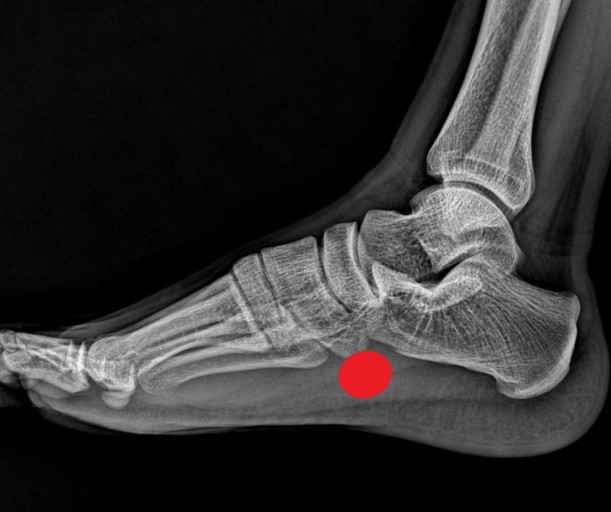

초기에는 밤에만 불편함을 느끼다가 점점 지속 시간도 늘어납니다.3. 족저근막염

발바닥 통증의 대표 질환으로,

발뒤꿈치에서 발바닥 전체로 이어지는 근막에 염증이 생기며

걷거나 서 있을 때 발바닥이 뜨겁고 찌릿한 통증을 유발합니다.

특히 아침에 첫 발을 디딜 때 더 아픈 경우가 많아요.